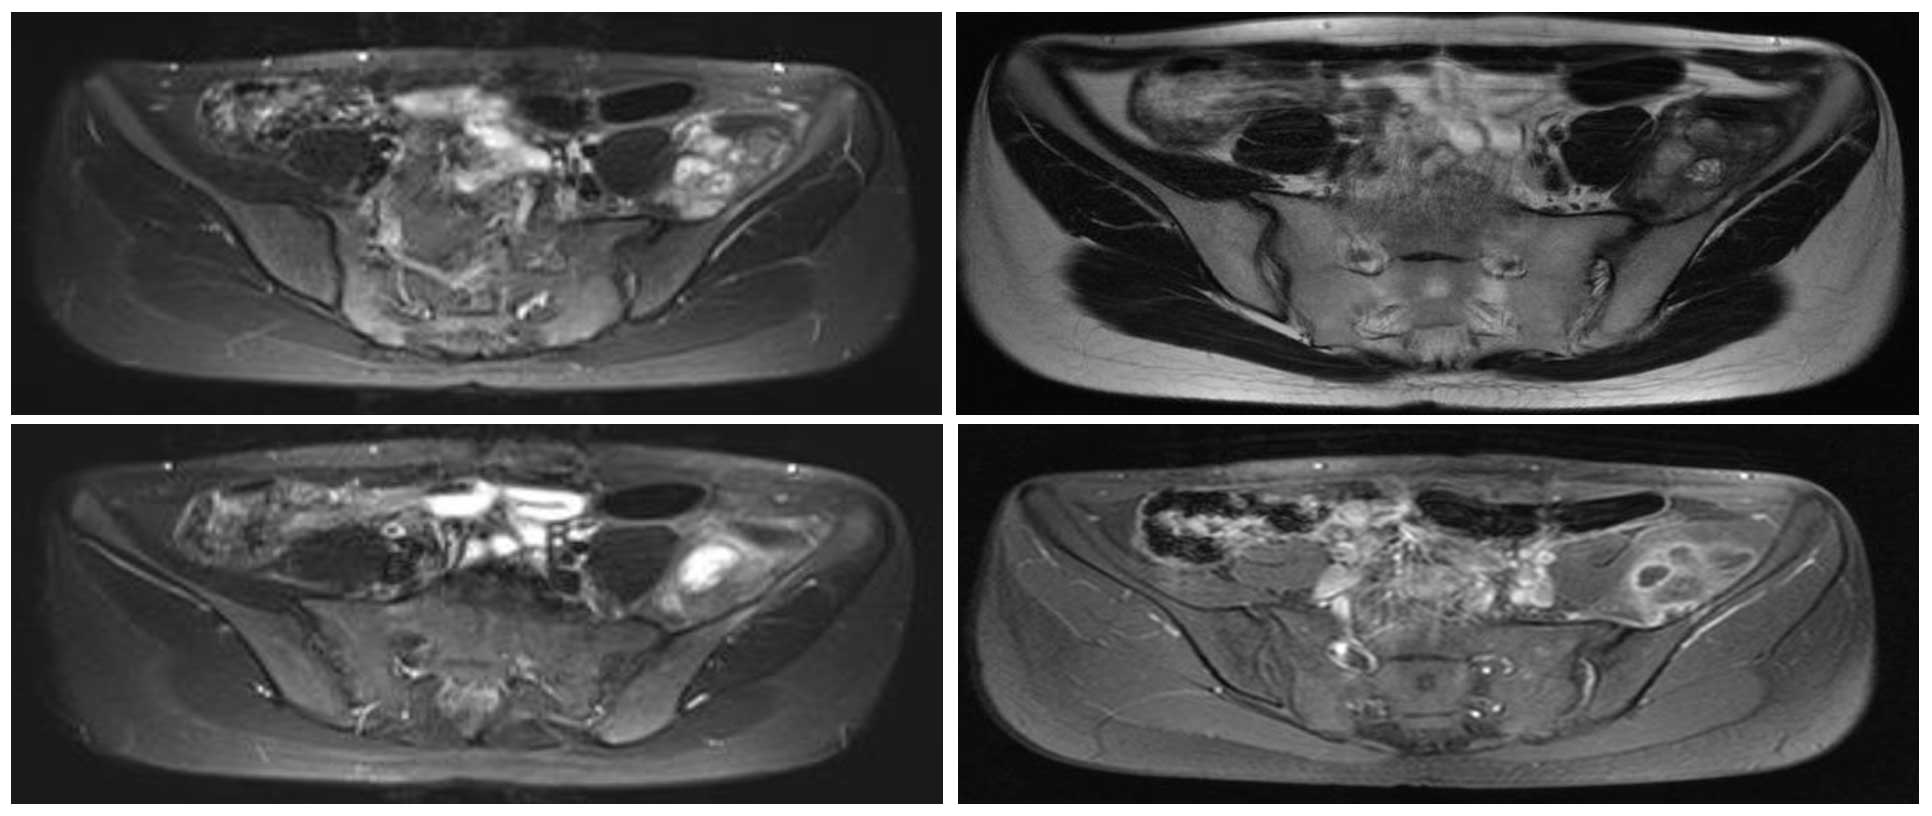

Ameliyat Öncesi: MR’da sol iliak kanat medialde düzensiz sınırlı, heterojen, periost reaksiyonunun eşlik ettiği tümör dokusu görülmekte.